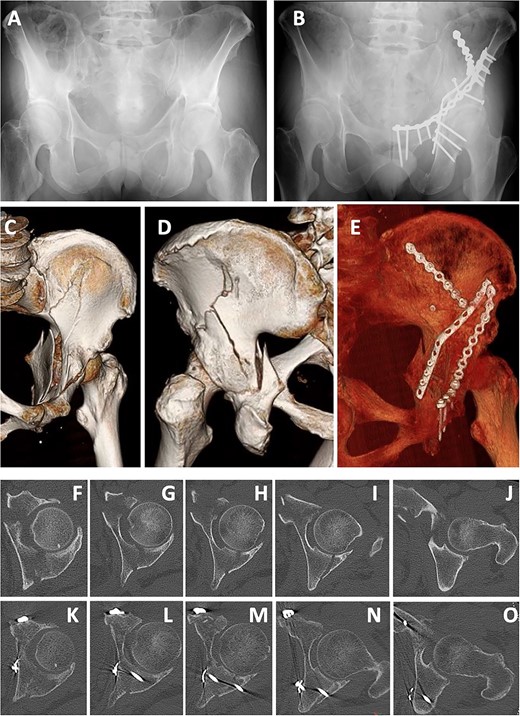

A 55-year-old man was involved in a motorcycle accident and taken to a nearby hospital. Diagnostic imaging showed a left acetabular fracture (Fig. 6A, C, D, F–J; both column fractures according to the AO classification). He was transferred to our hospital, and 12 days after the injury, open reduction and internal fixation were performed using a low-profile pelvic plate system (DePuySynthes Trauma, West Chester, PA, USA). The patient was placed in the supine position, and the classical ilioinguinal approach was used. The skin was cut from the pubic joint to the iliac crest, the abdominal muscles were released, and the retroperitoneal area and the fracture area were reached. Dislocation of the pelvic brim was reduced with a reduction clamp and fixed by a screw. After the internal obturator muscle was retracted, the quadrilateral fragment was reduced, a bent 12-hole, one-third plate was placed at the quadrilateral surface, and a screw was inserted from the posterior column to the ilium using the sleeve guide technique (Fig. 6K–O). In addition, two reconstruction plates were used for fixation from the anterior to the posterior ilium and from the pubis to the ilium (Fig. 6B, E). Six weeks after the operation, partial weight-bearing was started. After 3 months, the patient walked with a stick. After 1 year, he reported no hip or pelvic pain, and he walked without a gait abnormality.

Case 1 images: (A) pre-operative X-ray, (B) post-operative X-ray, (C) pre-operative 3D-CT (anterior), (D) pre-operative 3D-CT (posterior), (E) post-operative 3D-CT, (F–J) pre-operative axial CT images, (K–O) post-operative axial CT.